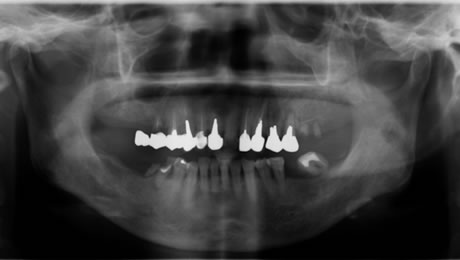

下のレントゲンと口腔内写真は先日インプラント治療が終わった患者さんの初診時です。

いままで仕事が忙しく、口内清掃が不良で歯が喪失していました。

仕事をリタイヤし、これからの人生を快適に過ごすため口腔内をしっかり治したいので来院されました。

Before

歯石の沈着、プラークコントロール不良で、歯肉の発赤がみられます。

奥歯は歯周病、虫歯を放置していたため歯が喪失しています。